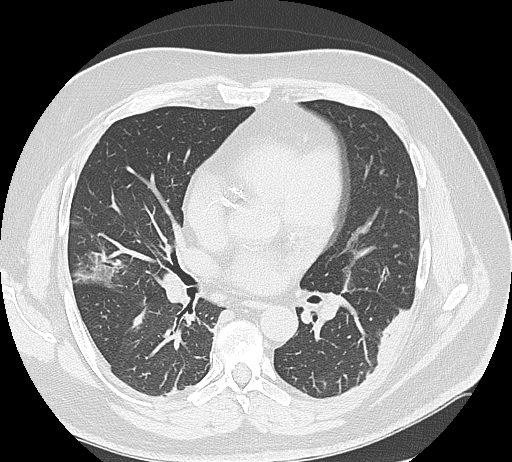

43-year-old male patient

with fever, cough. No previous medical history. Exposure to Covid-19 patients.

Respiratory failure (hypoxemia and hypercapnia). Leukopenia. Nasal swab positive for SARS-CoV-2.

HRCT

Figura 1